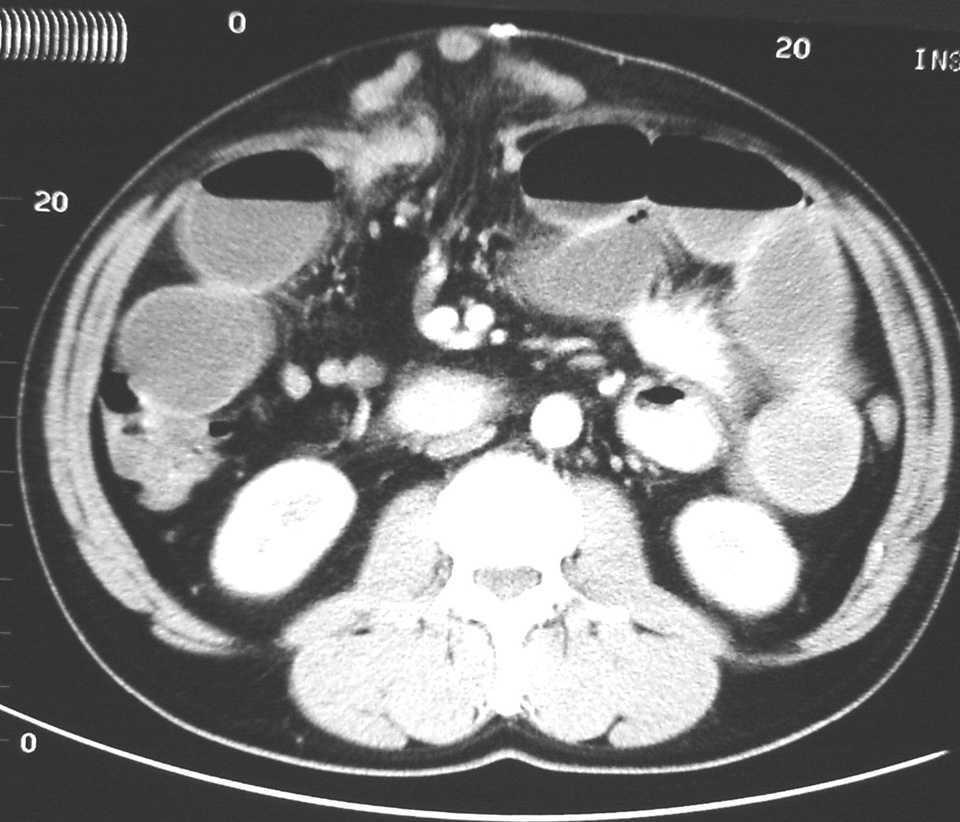

En la presentación clínica predominó el manchado del apósito en 44 casos (77%), el íleo paralítico en 43 (75,5%), el abultamiento de la herida en 28 pacientes (49%), dolor abdominal en 20 (35%), náuseas y vómitos en 18 (31,5%), tos en 8 (14%) y ascitis en 3 (5%). La analítica mostró leucocitosis, con o sin desviación a la izquierda, e hipoproteinemia en el 89,5% (51 casos), anemia con descenso de la hemoglobina y el hematócrito en el 73,5% (42 casos), y uremia con aumento de la urea y la creatinina en el 52,5% (30 casos). En alguno de los casos fue de gran ayuda la realización de una tomografía computarizada (TC) abdominal (fig. 2). El germen más aislado en los cultivos fue Escherichia coli (tabla 6).

Fig. 2. Tomografía computarizada abdominal: se aprecia la salida de intestino delgado por una dehiscencia de la aponeurosis tras la realización de una laparotomía media.